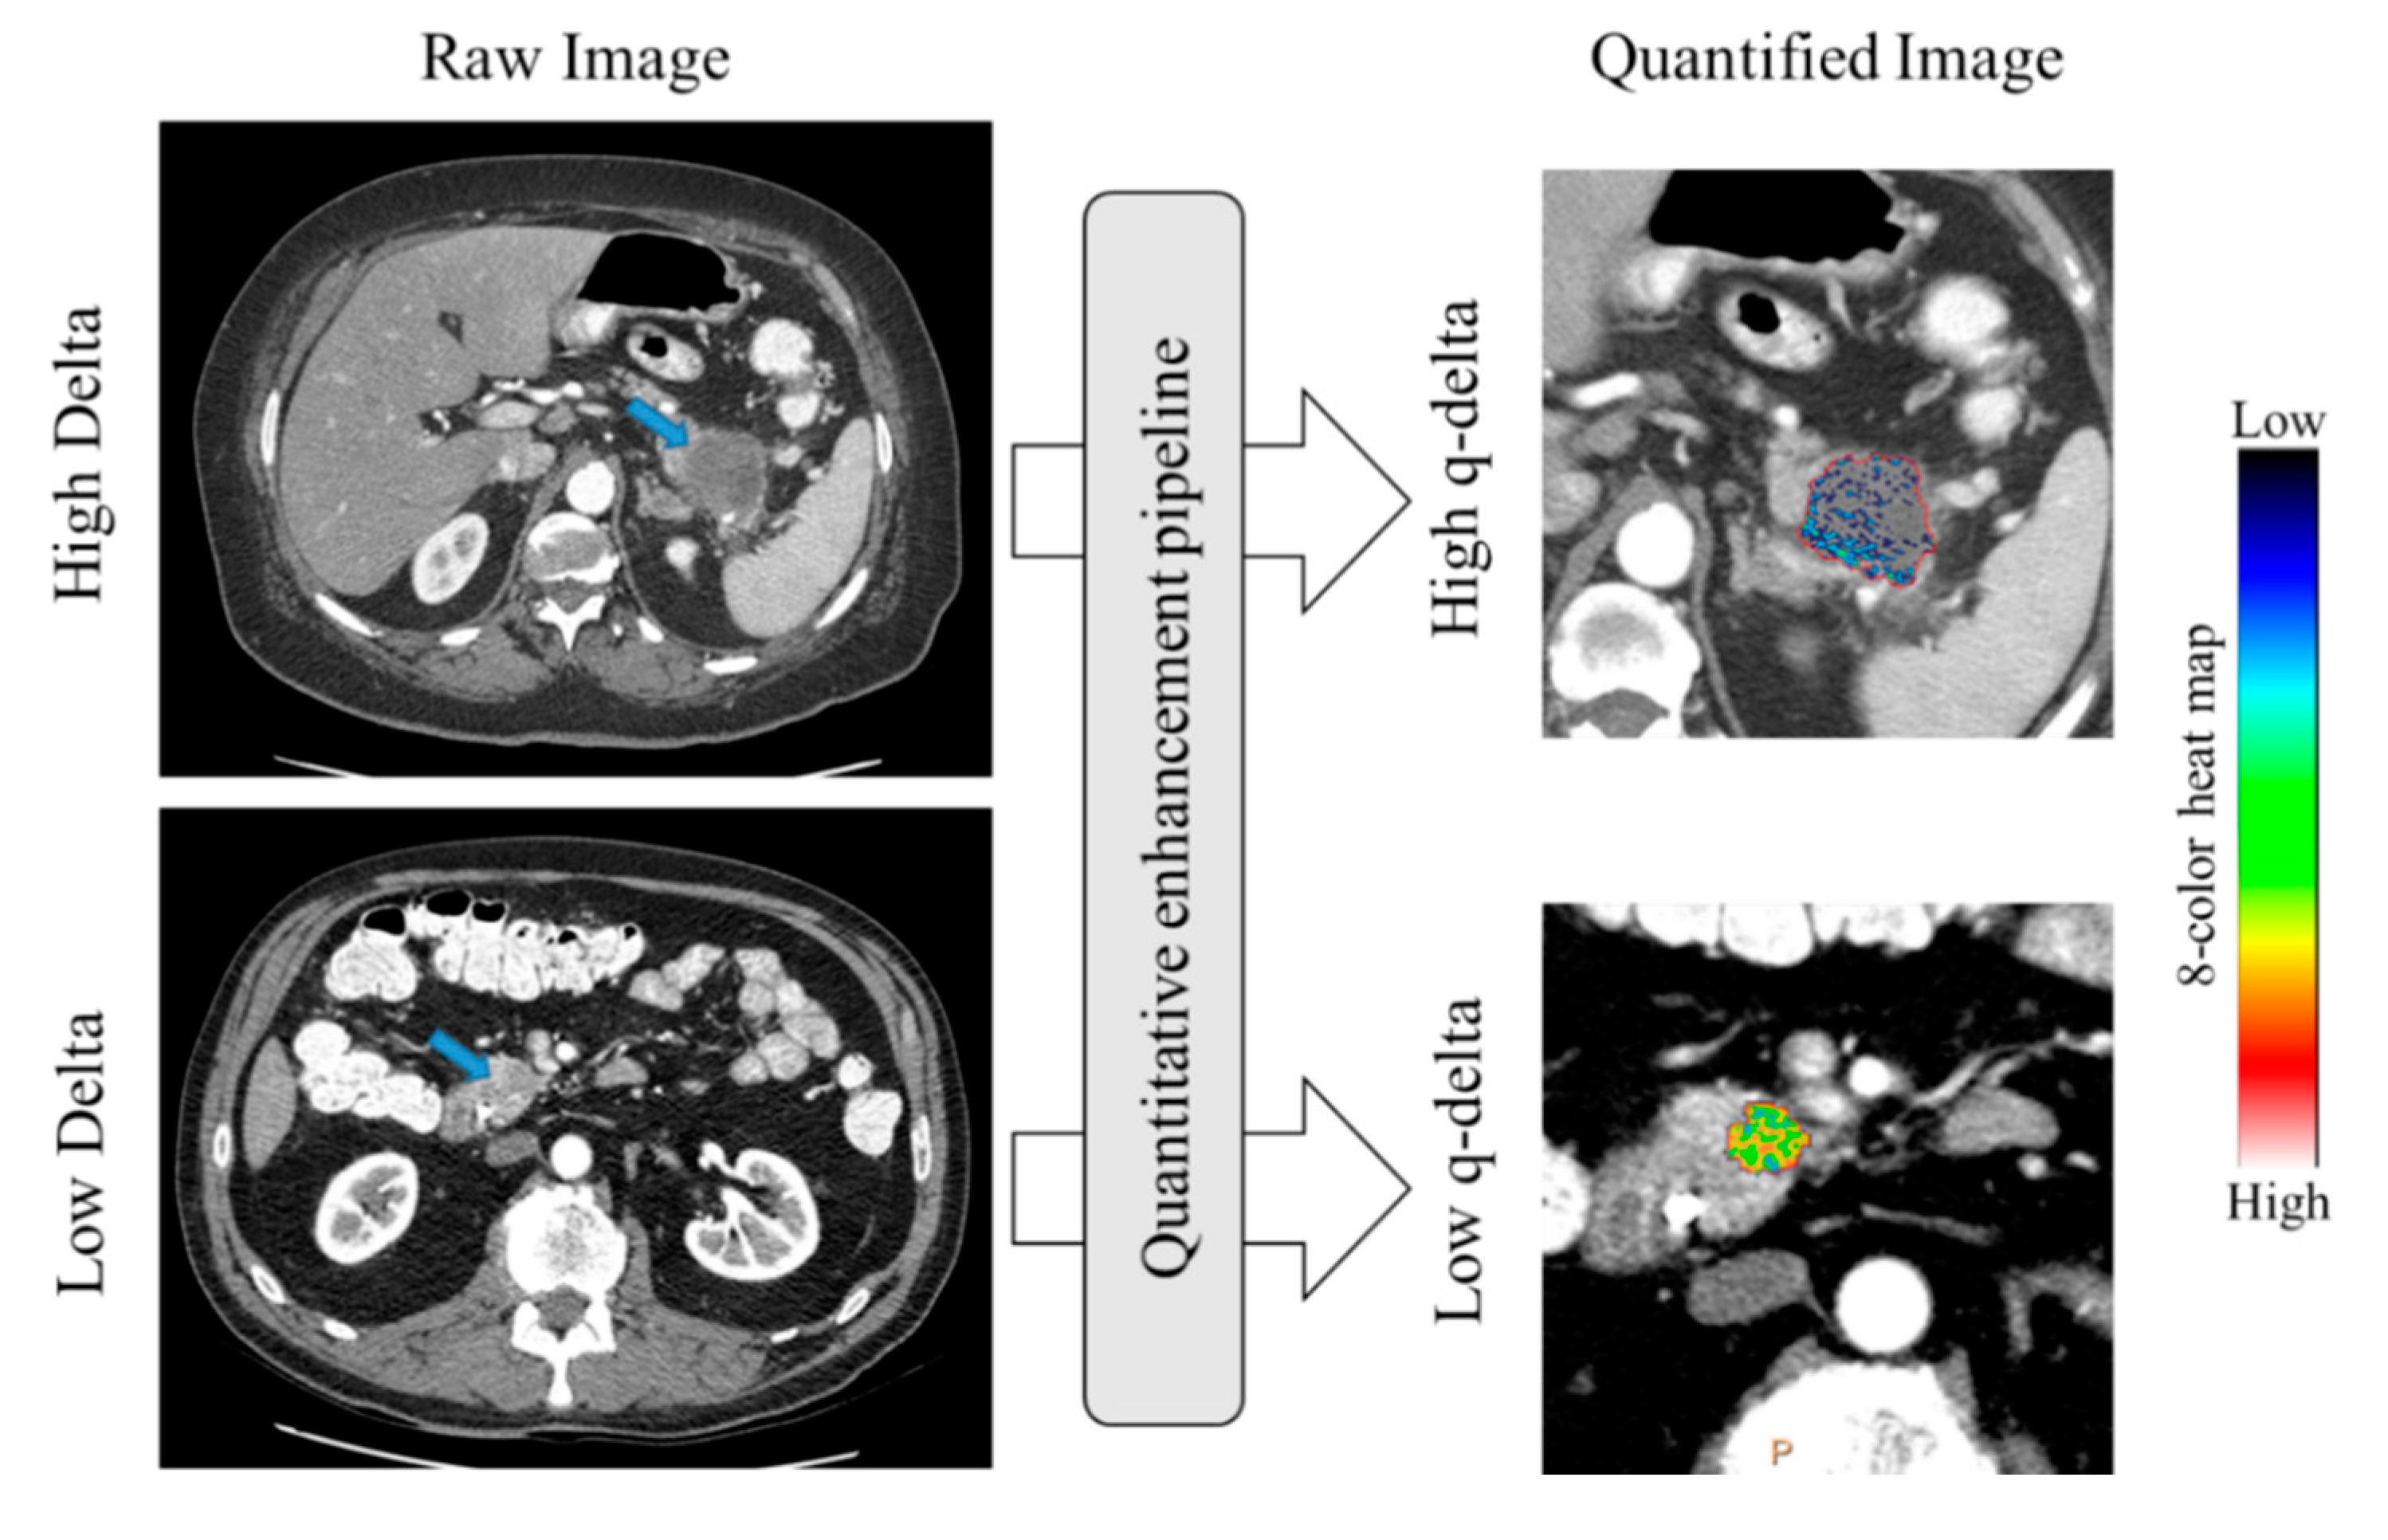

1. Introduction

4.4. CT Analysis: Qualitative Delta Scoring

4.5. CT Analysis: Quantitative Normalized Enhancement (q-delta)